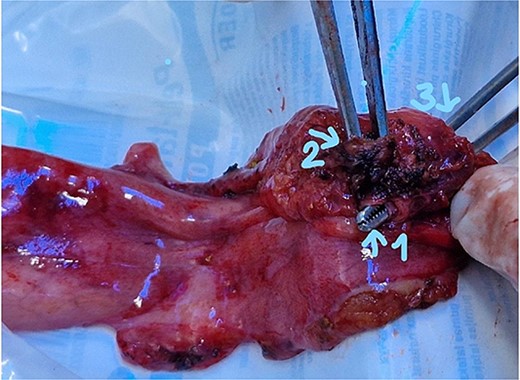

The patient was scheduled for a laparoscopic cholecystectomy the following day. Intraoperatively, an enlarged gallbladder hydrops with the presence of various caliber calculi in the lumen, the largest of which measured 2 cm/d, was found. The contents of the bladder are punctured and evacuated to facilitate its grasping in the fundus area and creating a good exposure of Callot’s triangle. Using a four trocar technique, a dissection was performed in the triangle of Callot, noting the difficult manipulation in the area between cystic duct and common hepatic duct. The cystic duct is identified to its confluence with the common bile duct at a 45° angle. The cystic artery was also visualized, after which clips were placed on both structures after ensuring that they entered the gallbladder. Dissection of the gallbladder in its distal part, attached to the liver parenchyma above Rouvier’s line, was started using electrocautery and hook. The tissue density of a limited area in the distal part between the wall of the gallbladder and the liver parenchyma was dissected using a hook. A bile duct was opened in its unusual anatomical location (Fig. 1). Due to lack of equipment for intraoperative cholangiography, it was converted to open access and subsequent revision of the extrahepatic bile ducts. The common bile duct and right–left hepatic duct were mobilized to the site of entry into the liver parenchyma. A parietal lesion of the right hepatic duct just above the confluence and anatomical integrity of the common bile duct and left hepatic duct were found. After examining the removed gallbladder, it was found that it was immediately flowing into a duct which connects the cystic duct with the right hepatic duct as depicted in Fig. 2. A plasty of the right hepatic duct was performed, and prior to this duodenotomy and papillotomy were performed by mobilization of the duodenum according to Kocher. A protective drain was placed in the choledochus draining from the right hepatic duct to the ampulla of Vater. Separetely, the clips previously placed on the cystic duct were removed and a transcystic drain was placed; a leak test was performed at the plastic site of the right hepatic duct. The postoperative period was without complications. From the transcystic drain, the secretion of bile stopped on the fourth postoperative day. On the eighth postoperative day, transdrainage cholangiography was performed; the common bile duct and bought hepatic ducts were imaged, and free passage of the contrast material through the duodenum was established (Fig. 3). The transcystic draine was removed on the 20th day of surgery.

Visualization of the biliary lesion; (1) tangential damage to the right hepatic duct; (2) gallbladder with lateral traction.